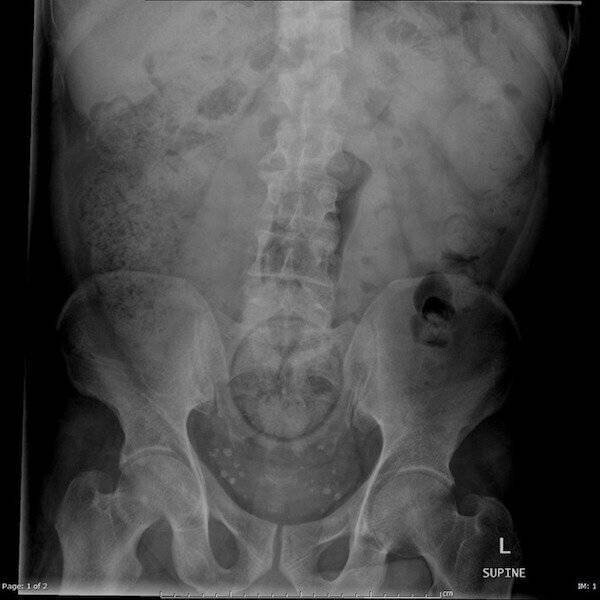

3. Апельсин